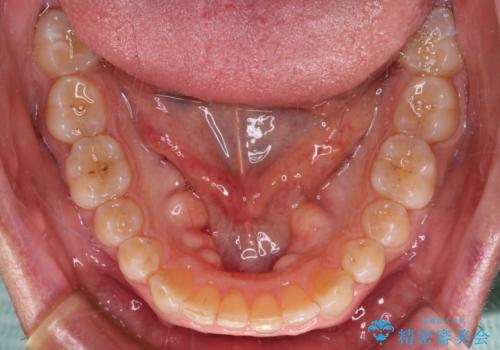

- 前歯のデコボコを気にして来院された患者様です。

インビザラインでもワイヤー装置でも対応可能でしたが、仕事の都合で来院回数を減らしたいとのことでインビザラインによる矯正治療を選択されました。

著しく咬合力が強いため、奥歯がしっかりと噛めずに治療が長引くことが懸念されました。

1セット目のインビザラインを使用した際には左右ともに大臼歯が咬み合っていなかったのですが、2セット目できっちりと仕上げることができました。